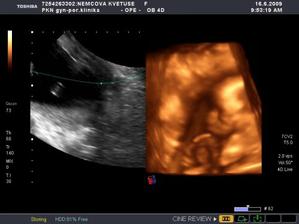

Nová naděje. Bohužel to bylo opět stejné, jako již dvakrát předtím. Třetí revize, třetí ztráta naděje. Jsem po laparoskopii a hysteroskopii a čekáme na výsledky imunologie v Plzni. Pak se uvidí co dál. V únoru 2009 nám v Sanusu doporučili ještě dva měsíce domácího snažení. Tak jsme se snažili a nyní napjatě sledujeme čárku. HCG nám krásně stoupá, 20. den po ovulaci je 2066. Máme 1. fotku dutinky. Přes nejrůznější potíže a patnáctidenní hospitalizaci nám miminko krásně roste. 22. dubna konečně po čtrnácti dnech ukázalo nosánek, máme nosní kůstku, NT je 2,0. Máme vše, co máme mít a rodiče se dnes poprvé společně dívali na ultrazvuk. Viděli mě i 4D, to koukali. Odnesli si video a teď na něj pořád koukají. Další kontrola náš čeká 5. května, opět ultrazvuk, triple testy a poradna. Trošku změna situace, mamka se mnou leží od 27. dubna v nemocnici, ale já ji dělám radost, rostu, 16.6. už vážím 360 gramů a od 5.6. ji kopu a ona o tom ví. Od 10. 6. se nám začal malinko měnit nález až jsme museli 10. 7., gr. h. 24+2 na cerclage, potom jsme měli zánět ledvin a astmatický záchvat. Pořád mamce tvrdlo břicho, tak se bez infuzí neobejde. 18. 7. se ještě objevilo krvácení, ale nebylo to nic závažného, byli jsme na ultrazvuku a vážím 908 gramů. V pátek 24.7. se to zlepšilo a kapeme na nejnižší rychlost, hurá. Mamka zatím nesmí chodit, má to slíbeno na 2. září. Kapeme sice na nejvyšší rychlosti, ale na ultrazvuku 4.8. mám odhad 1280 gramů. Dne 18.8. jsme byli na ultrazvuku a mám odhad 1750 gramů, mám trochu víc plodové vody a tak si tam plavu jako v bazénku. Dne 28.8. jsme byli s mamkou zase na ultrazvuku, vážím už 1950 gramů, mám udělaný krásný 3D fotečky, vody už nemám tolik moc, tak je mamka ráda. Jen se nám zase zkrátil čípek, už mě tam drží jen steh a 13 mm, ale držím mamce pěstičky, aby jsme vydrželi. No a taky si musím zvykat, mamka totiž má už dovoleno chodit na wc, a já jsem byl zvyklej, že pořád leží. Je sice z toho unavená, ale šťastná. Já jsem jí ještě udělal radost, že jsem se přetočil hlavičkou dolů. Dne 1.9. se mi konečně podařilo zbavit se té nitě, co tam mamka měla. Všichni jsou překvapení, jak se to mohlo stát, ale steh je pryč. Dne 10. 9. jsme s mamkou byli zase na ultrazvuku, vážím 2368 gramů (33+1). Hrdlo máme sice jen 9 mm, ale já se tam ještě udržím! Plodové vody mám už akorát, mamce klesly jaterní testy, žlučové kyseliny jsou v normě, tak má radost. Tak dnes 17. 9. jsem se byl zase vážit, mám 2517 gramů. Hrdlo má mamka jen 6,7 mm s obrovitým funnelingem, ale pořád drží. Denně mi točí monitory, mám je vzorné a pořád nemůžu přijít na to, jak ty sondy odkopnout. 26.9. pustil pan doktor mamku na propustku, byla poprvé 12 hodin mimo nemocnici, byli jsme na zahradě, grilovali jsme a já jsem babičce, dědečkovi a strejdovi předváděl, jak umím krásně kopat. Mamka byla moc šťastná. Večer se vrátila do nemocnice, dala si po 23. hodině sprchu a když usínala, tak jsem ji hodně překvapil, vypustil jsem svůj bazén. A tak se nešlo spinkat, ale na porodní sál. Šlo to pěkně a přesně ve 4.00 hodin jsem se narodil za skvělé asistence mého tatínka, který mamince na sále moc pomáhal. Vážím 2740 gramů a měřím 50 cm. Dosáhl jsem gestačního stáří 35+4. Rodiče a velká spousta lidí kolem ze mě mají velikánskou radost. Trošku jsem odmítal v inkubátoru dýchat, tak mě 1 den pomáhal CPAP. Večer mi ho vzali a teď už se snažím sám. mamka za mnou chodí a já jsem rád, když ji vídím. Dnes jsem na ni poprvé otevřel očička, snažím se papat, dnes už ze stříkačky. Tatínek je ze mě unešenej a já jsem rád, když mě přijde pohladit a vyfotit.